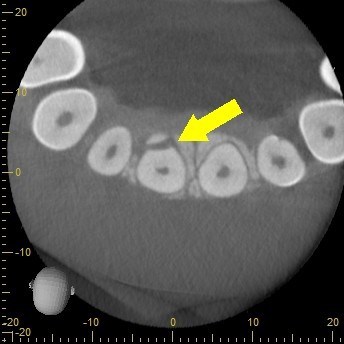

Lastly, I decided to take a CBCT to rule out any abnormality. To my surprise, a portion of the tooth had fractured off and become dislodged lingual to the tooth. Fortunately, the segment was removed easily and the patient’s symptoms resolved immediately.

The ability to take a CBCT and have it as part of our arsenal for diagnostic procedures is sometimes not readily appreciated. In this case, it was only through the CBCT that we could diagnose the cause of his symptoms and thereby treat the patient quickly.